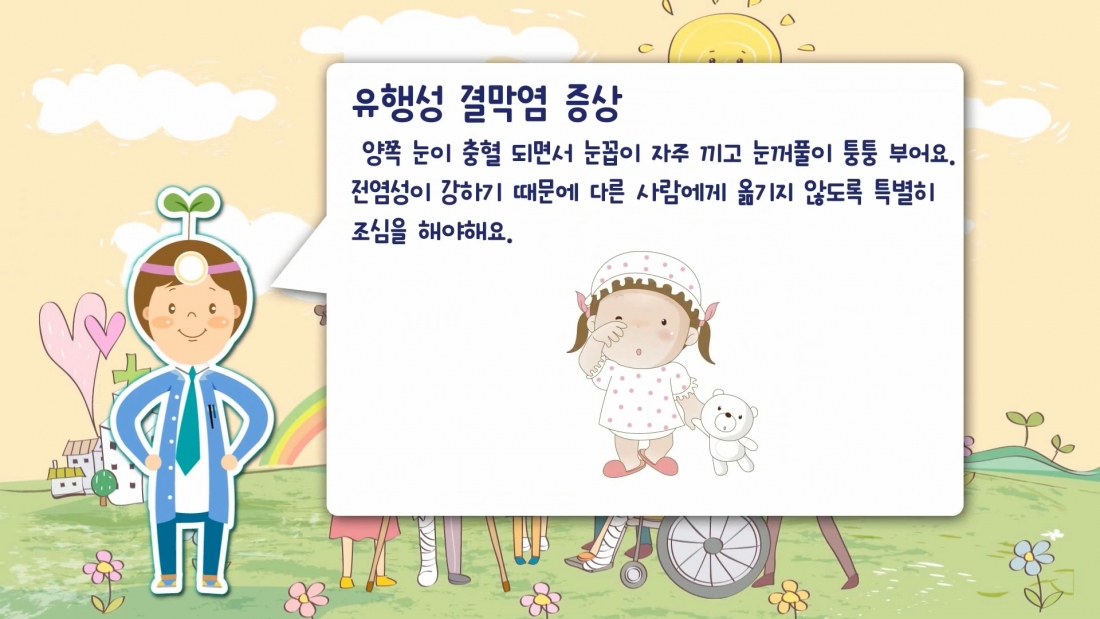

안전교육-여름철 질병을 예방…